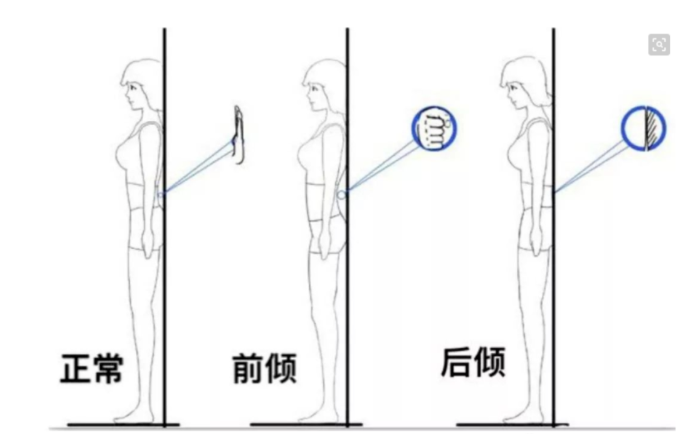

中立位

我们这里先说侧面看的体态中立位。如下图,如果我从天花板挂一个铅垂线,让线穿过你的脚一侧的外踝,体态好的人,线会穿过你的膝盖前 1 / 3 处,骨盆大转子,肩峰和耳垂。如果有任何的偏离,都基本说明体态出现了问题。

通过侧面观察,我们能发现自己在矢状面(前后) 的体态问题。正常状态下,人类 的身体中这五个点应该近似位于一条直线的:耳垂、肩峰、股骨大转子、股骨外髁、外踝。

由于人类的大量运动是在矢状面进行的,因此从侧面观最容易发现体态问题,所以我们一般会以侧面观察作为体态评估的开始 。人体的五个主要关节在矢状面的功能紊乱会导致一系列的代偿现象,常见的矢状面体态问题包括骨盆前倾、骨盆后倾、圆肩探头、驼背等。